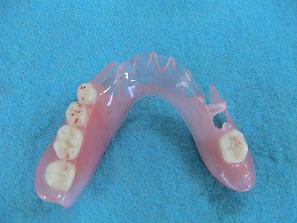

2. 作製したバネなし入れ歯

(バルプラスト)です